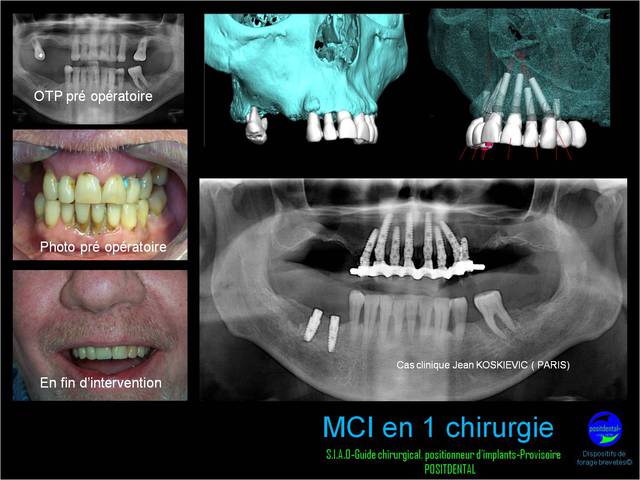

à 6 mois de l'implantation